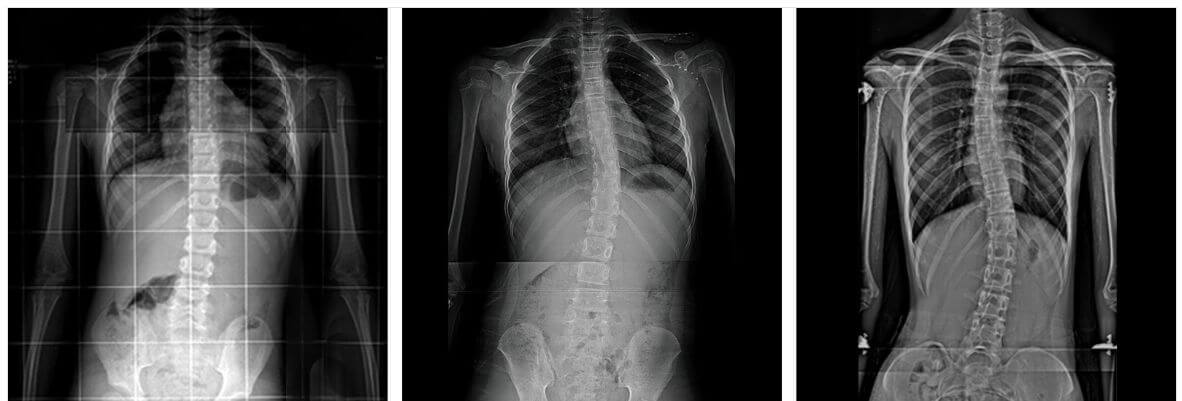

우리가 흔히 척추측만증으로 부르는 척추옆굽음증은 척추의 형태가 앞, 뒤, 좌, 우 혹은 복합형으로 틀어지고 휘어진 형태를 말합니다.

X-ray검사를 하면 척추뼈의 기형을 비교적 쉽게 발견할 수 있습니다.

측만증의 심한 정도는 각도로 표시하며, 이 각도의 정확한 명칭은 콥스각(Cobb's angle)이라 합니다. 이 각도가 몇 도인지 알아야 치료를 결정할 수 있습니다.

25도가 넘으로면 외관상의 변화가 나타나고, 45도 이상이면 수술적 치료대상이 됩니다.